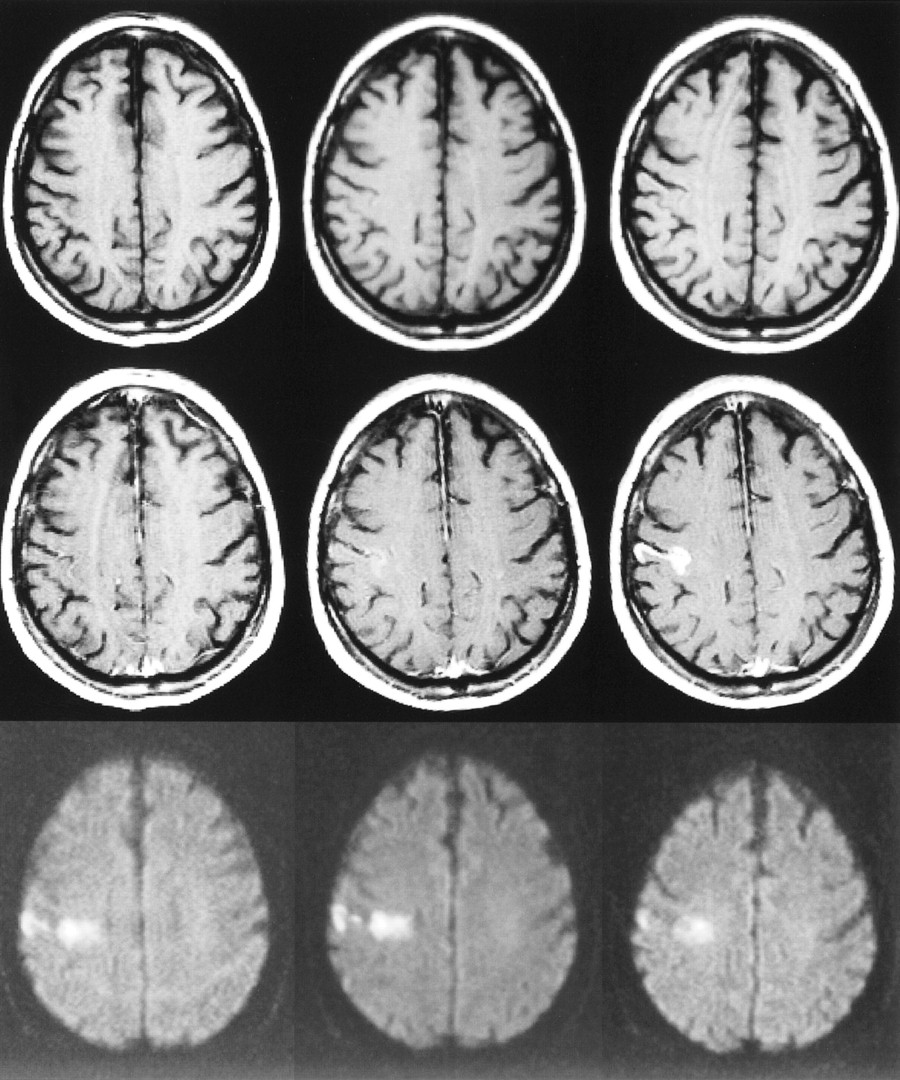

63-year-old woman with right hemiparesis and aphasia. The first MR examination (left column) was performed 6.5 hours after the onset of symptoms, the second MR examination (middle column) was performed on the second day, and the third MR examination (right column) 1 week after stroke.

Top row, Unenhanced T1-weighted images (600/14/1) show progressing low signal mass effect of the infarcted tissue. Hemorrhagic transformation is detected as areas of increased signal intensity on the second day and at 1 week. The gyral pattern of increased signal intensity at 1 week may also represent cortical laminar necrosis.

Middle row, Contrast-enhanced T1-weighted images (600/14/1) show intravascular enhancement over the infarct on the first and second days. Moderate cortical and deep enhancement is detected at 1 week.

Bottom row, Diffusion-weighted trace images (4000/103/1, in raw image acquisition) show the extent of infarcted tissue as areas of increased signal intensity in the territory of the left middle cerebral artery. Hemorrhagic transformation is detected as a dark area due to the susceptibility effect of breakdown products of hemoglobin.